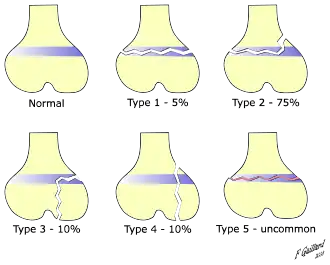

There are nine types of Salter–Harris fractures; types I to V as described by Robert B. Salter and William H. Harris in 1963,[3] and the rarer types VI to IX which have been added subsequently:[5]

- Type I – transverse fracture through the growth plate (also referred to as the "physis"):[6] 6% incidence

- Type II – A fracture through the growth plate and the metaphysis, sparing the epiphysis:[7] 75% incidence, takes approximately 12-90 weeks or more in the spine to heal.[8]

- Type III – A fracture through growth plate and epiphysis, sparing the metaphysis:[9] 8% incidence

- Type IV – A fracture through all three elements of the bone, the growth plate, metaphysis, and epiphysis:[10] 10% incidence

- Type V – A compression fracture of the growth plate (resulting in a decrease in the perceived space between the epiphysis and metaphysis on x-ray):[11] 1% incidence